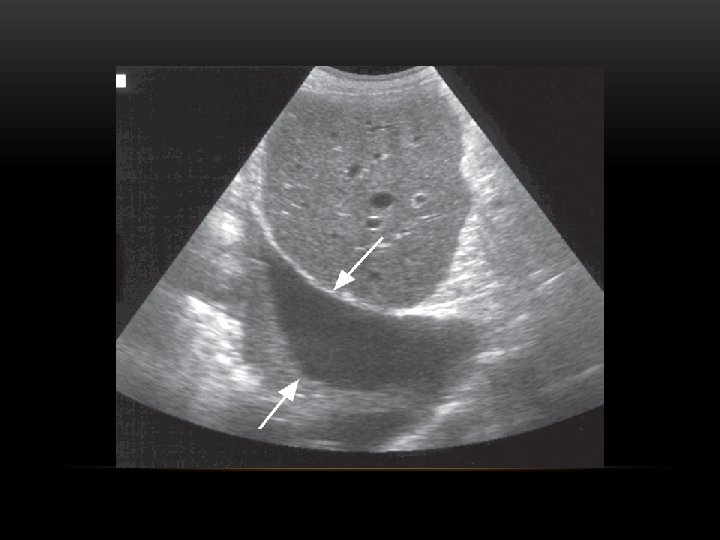

Pneumothorax is air in the pleural space. Radiological criteria: Air (black) in pleural space. No lung markings in pleural space. Recognition of atelectatic lung (lung margin). The lung recoils to a resting state as the negative pressure in the pleura is lost (relaxation atelectasis).

Pneumothorax • No vascular markings on right • No shift of mediastinum to left • Atelectasis right lung • Increased haziness on left: Diversion of entire cardiac output • Small fluid level near costophrenic angle: Hydro pneumothorax

Hydropneumothorax